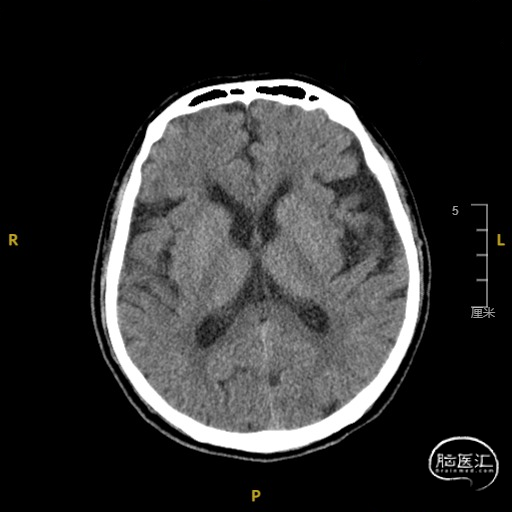

➢ 入院后头核磁检查

患者主因言语不利3天入院,头核磁提示右侧额、顶叶多发低灌注梗塞,脑血管造影提示右侧颈内动脉开口重度狭窄,为责任血管,另外患者前交通动脉、右侧后交通动脉开放不良,并且狭窄严重,考虑到高灌注风险,决定分期处理,一期小球囊扩张改善供血,二期支架成型。